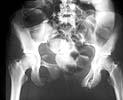

The patient sustained multiple injuries 11 months previously, including the pelvic ring disruption seen in the attached photos. The anterior injury was a fracture through the left pubis; the posterior lesion was a vertical fracture of the sacrum.

The Xrays and CT's provided show evidence of a Right sacral ala fracture, healed without significant vertical displacement or rotational abnormality. There is no evidence of external rotation through either of the SI joints. I see no evidence of there being a nonunion of a sacral fracture. I am unclear about the original purpose of the iliosacral fixation. Perhaps pre-op Xrays prior to this procedure would be helpful. In any event, there does not appear to be a substantial posterior pelvic ring deformity at this time. This is supported by the current AP pelvis which demonstrates well defined ilioischial lines bilaterally with a well positioned AP of the sacrum.

The anterior pelvic ring injury probably consisted of Bilateral superior and inferior ramus fractures as well as a fracture of the body of the pubis. The rami have united with the large anterior diastasis. I believe, therefore, that this is an isolated malunion of the anterior pelvic ring ocurring through 3 sites, the rami bilaterally and the body of the L pubis.

This is a difficult deformity. The initial anterior ring injury looks sort of lined up on the ex/fix films yet later on there is a large anterior gap. The posterior ring injury looks lined up. That seems incorrect. How could there be such deformity anteriorly and little or none visible posteriorly?